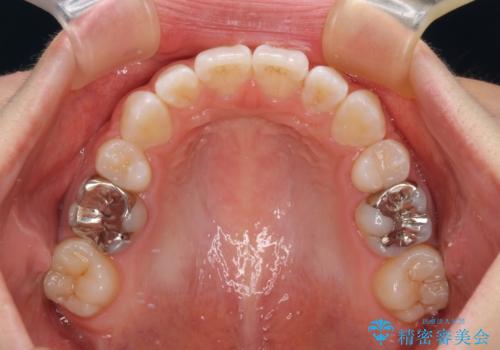

- クリアブラケット

- 1年6ヶ月

- 前歯の出っ歯と口元の閉じにくさを気にして来院された患者様です。

口元を積極的に引っ込めるために、上下左右の小臼歯4本を抜歯することとしました。

4本の歯を抜歯したことで、飛び出していた口元が引っ込み、横顔が大きく改善されました。